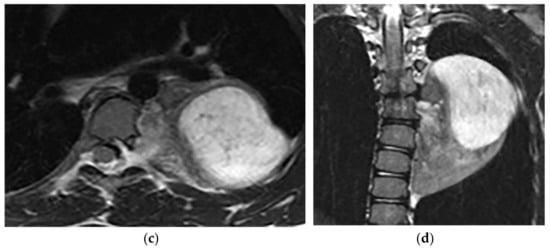

Neuroblastoma appears as an ill-defined paravertebral soft tissue mass on a CT scan with heterogeneous attenuation caused by hemorrhage, necrosis, or cystic degeneration. Internal calcification is seen at least in 30% of cases [7,16]. MRI shows irregular margin with possible local invasion to the spinal canal, presenting T1-hypointensity and T2-hyperintensity with heterogeneous enhancement. Calcification has a signal void in all sequences (Figure 18 and Figure 19). It is reported that tumors with higher metabolic activity on 18F-FDG PET/CT have lower overall survival [44,45]. Metaiodobenzylguanidine labeled as 123I (MIBG) is highly sensitive for detecting catecholamine-producing tumors like neuroblastoma [7,16].

Figure 18.

A 6-year-old boy with posterior mediastinal mass with histopathological confirmation for Neuroblastoma. Axial (a) T2W shows an ill-defined lobulated group (arrow) with heterogeneous and hyper-intense signal intensity and area of a signal void within the posterior mediastinum. It has intracanal extension via right-sided neural foramina and extradural components at multiple levels. It displaced the spinal cord anteriorly, as shown in sagittal T1W after gadolinium administration (arrow) (b).

Figure 19.

A 4-year-old girl with the opsomyoclonus-myoclonus syndrome. Sagittal (a) and axial (b) T2W images show large lobulated paraspinal masses (arrowhead) crossing the midline within the posterior superior mediastinum. It shows heterogeneous and hyperintense signal intensity with internal foci of the signal void caused by calcification. It extends through the spinal canal via neural foramina (arrow). Right anterolateral displacement of mediastinal great vessels is also identified.